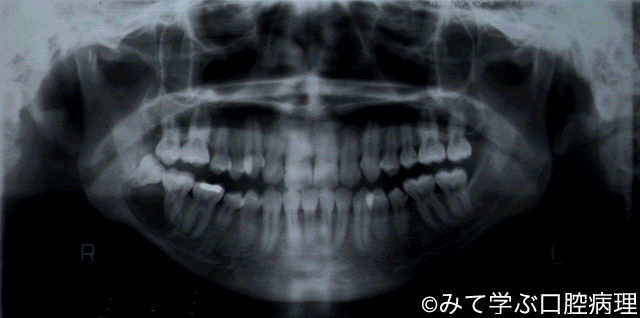

原始性嚢胞

右第二大臼歯と第三大臼歯の歯根が離開して嚢胞がみえる